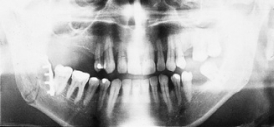

Osteosynthesis procedures are performed at our clinic according to modern international standards. Mini and micro plates made of titanium and special medical steel are used to stabilize the fractured bones. Especially for the treatment of temporomandibular joint fractures a joint plate was developed in our clinic. The development and application of resorbable osteosynthesis materials is at the same time a research task of the clinic.